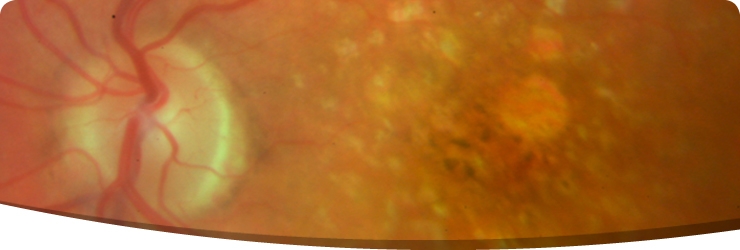

Dry AMDDrusen

Aging changes at the back of the eye ( AMD ) involve the part of the eye responsible for central vision. This part of the eye is called the macula and is the central portion of the retina. This condition can take two major forms termed dry and wet. The dry form of the condition is much more common than the wet form and generally causes less serious vision decline. This type of AMD is also likely to progress much more slowly than wet AMD . On average 80-90% of people with AMD  will have the dry form of the condition. The other 10 to 20% will have the wet form. Milder forms of dry AMD can often be present without noticeable vision decline.

The first sign of dry AMD is often the development of tiny yellow grain like deposits under the retina. These often start being small in size and gradually, often over many years, grow larger in size and increase in number. These deposits are called drusen. It is now recognised that people with just a few small drusen will have a very low chance of developing more advanced AMD over a five year period (around 1.3%) compared to a much higher risk of developing more advanced AMD in those who have already developed some larger drusen bodies.Later signs of dry AMD may include gradual loss of specialised cells called retinal pigment epithelial cells (RPE). These cells act as the nutritional support system for the retina. Patchy loss of these cells is fairly common even early on in the AMD process but with time the patchy areas of RPE cell loss may coalesce and form larger islands of cell loss - a finding termed geographic atrophy. This stage of dry AMD is often associated with poor vision and is one of the types of AMD termed advanced.

Drusen

drusen2